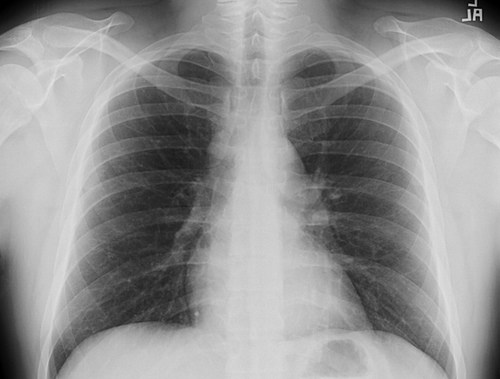

CT scans and Chest x-rays

Computed tomography (CT scans) and chest x-rays may be performed to detect an enlarged thymus (thymoma), which is common in MG.